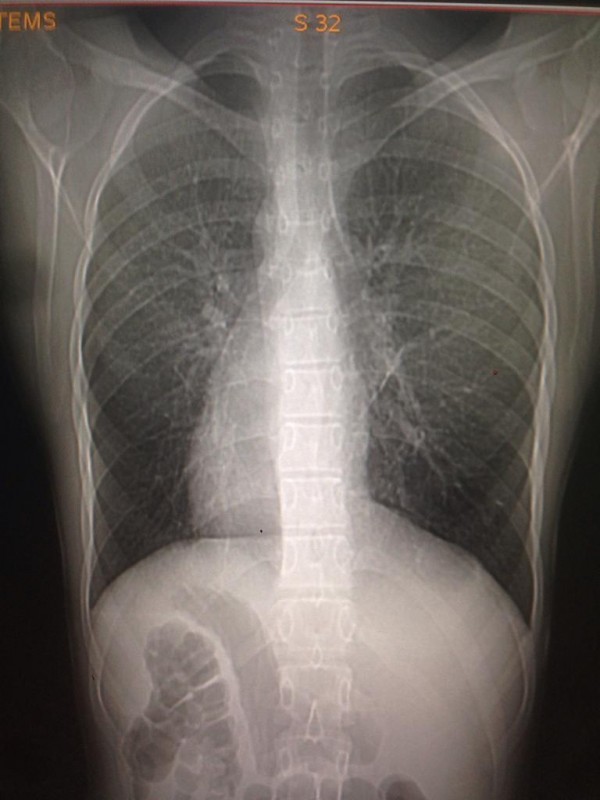

Транспозиция внутренних органов. Снимок предоставлен Сундетом Саргеловым

Транспозиция внутренних органов - редкий вариант биологически нормальной анатомии, в котором основные внутренние органы имеют зеркальное расположение по сравнению с обычным нормальным положением: сердце - справа, печень - слева, желудок - справа. Такой случай встречается у одного человека из 10 тысяч. Главная причина - мутация генов, и передается аномалия по наследству.

К сожалению, точных статистических данных обо всех казахстанцах, сердце которых расположено с правой стороны грудной клетки, нет. Однако, по словам медработника, в нашей стране ситуация аналогична мировой. Таким образом, если население Казахстана в среднем составляет 18 миллионов, то по вычету получается, что среди нас живет около 1800 правосердечников. В основном люди узнают об аномалии, когда делают рентген. К тому же зачастую посмертное вскрытие не проводят, так как родные умершего бывают против этой процедуры.